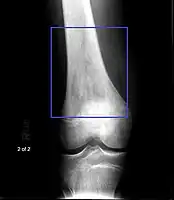

-

Osteosarcoma of the distal femur -

Metastatic osteosarcoma to the left chest -

Telangiectactic osteosarcoma of the humerus

Family physicians and orthopedists rarely see a malignant bone tumor (most bone tumors are benign). The route to osteosarcoma diagnosis usually begins with an X-ray, continues with a combination of scans (CT scan, PET scan, bone scan, MRI) and ends with a surgical biopsy. A characteristic often seen in an X-ray is Codman's triangle, which is basically a subperiosteal lesion formed when the periosteum is raised due to the tumor. Films are suggestive, but bone biopsy is the only definitive method to determine whether a tumor is malignant or benign.